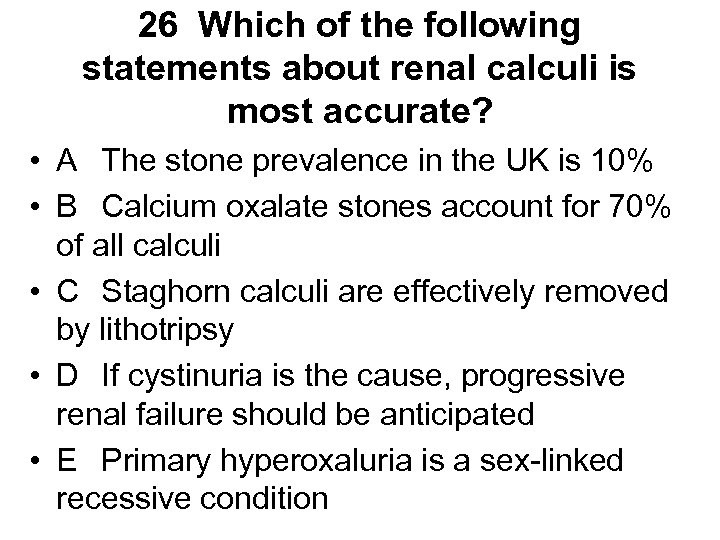

Lupus nephritis • Aetiology • - renal involvement occurs to some degree in most lupus patients, though drug induced lupus is said to spare the kidney • Presentation • - can vary from asymptomatic urine abnormalities to HT, NS, ARF, CRF • Diagnosis • - all patients with lupus and urine abnormalities should have biopsy to guide potentially toxic treatment regardless of serum creatinine. Histology can change from one type to another in the same patient. Six distinct patterns are recognised. Histology not similar to that of DN • 1 - normal • 2 a - mesangial deposits 2 b - mesangial hypercellularity • 3 - focal and segmental proliferative GN • 4 - diffuse proliferative (>50% glomeruli involved) causing RPGN • 5 - membranous • 6 - glomerulosclerosis

Lupus nephritis • Aetiology • - renal involvement occurs to some degree in most lupus patients, though drug induced lupus is said to spare the kidney • Presentation • - can vary from asymptomatic urine abnormalities to HT, NS, ARF, CRF • Diagnosis • - all patients with lupus and urine abnormalities should have biopsy to guide potentially toxic treatment regardless of serum creatinine. Histology can change from one type to another in the same patient. Six distinct patterns are recognised. Histology not similar to that of DN • 1 - normal • 2 a - mesangial deposits 2 b - mesangial hypercellularity • 3 - focal and segmental proliferative GN • 4 - diffuse proliferative (>50% glomeruli involved) causing RPGN • 5 - membranous • 6 - glomerulosclerosis

Lupus nephritis • • • Treatment 1 - no specific therapy 2 - steroids only 3 - steroids plus cytotoxic, may be cyclophosphamide 4 - steroids plus cytotoxic, usually cyclophosphamide 5 - controversial - likely to be steroids with azathioprine, mycophenolate or cyclosporin but not cyclophosphamide and not steroids alone 6 - controversial NB - cytotoxics indicated by histology and not simply by serum creatinine Outcome - glomerular sclerosis is most important predictor of ESRD - overall prognosis determined by presence or absence also of neuropsychiatric, cardiac and pulmonary disease

Lupus nephritis • • • Treatment 1 - no specific therapy 2 - steroids only 3 - steroids plus cytotoxic, may be cyclophosphamide 4 - steroids plus cytotoxic, usually cyclophosphamide 5 - controversial - likely to be steroids with azathioprine, mycophenolate or cyclosporin but not cyclophosphamide and not steroids alone 6 - controversial NB - cytotoxics indicated by histology and not simply by serum creatinine Outcome - glomerular sclerosis is most important predictor of ESRD - overall prognosis determined by presence or absence also of neuropsychiatric, cardiac and pulmonary disease